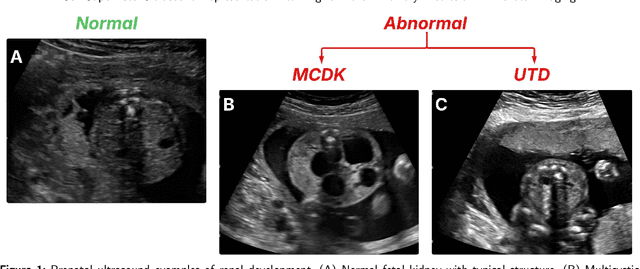

Abstract:Prenatal ultrasound is the cornerstone for detecting congenital anomalies of the kidneys and urinary tract, but diagnosis is limited by operator dependence and suboptimal imaging conditions. We sought to assess the performance of a self-supervised ultrasound foundation model for automated fetal renal anomaly classification using a curated dataset of 969 two-dimensional ultrasound images. A pretrained Ultrasound Self-Supervised Foundation Model with Masked Autoencoding (USF-MAE) was fine-tuned for binary and multi-class classification of normal kidneys, urinary tract dilation, and multicystic dysplastic kidney. Models were compared with a DenseNet-169 convolutional baseline using cross-validation and an independent test set. USF-MAE consistently improved upon the baseline across all evaluation metrics in both binary and multi-class settings. USF-MAE achieved an improvement of about 1.87% (AUC) and 7.8% (F1-score) on the validation set, 2.32% (AUC) and 4.33% (F1-score) on the independent holdout test set. The largest gains were observed in the multi-class setting, where the improvement in AUC was 16.28% and 46.15% in F1-score. To facilitate model interpretability, Score-CAM visualizations were adapted for a transformer architecture and show that model predictions were informed by known, clinically relevant renal structures, including the renal pelvis in urinary tract dilation and cystic regions in multicystic dysplastic kidney. These results show that ultrasound-specific self-supervised learning can generate a useful representation as a foundation for downstream diagnostic tasks. The proposed framework offers a robust, interpretable approach to support the prenatal detection of renal anomalies and demonstrates the promise of foundation models in obstetric imaging.